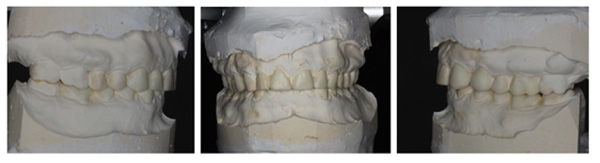

The patient was diagnosed with severe generalized tooth wearwith a significant acid erosion component. The multifactorial risk factors included acid erosion from drinking carbonated cola beverages and apple cider vinegar, plus the history of GORD. Stress-related parafunction or bruxism was also present. A detailed explanation of the risk factors and their consequences was given to the patient. The patient was advised to stop the intake of all acidic drinks and was monitored for 3 months. After this period, the patient was keen to proceed with rehabilitation but desired cost-effective care as he did not have private insurance and could not afford expensive treatment. To avoid costly laboratory work, informed consent was, therefore, gained for treatment using direct composite. Upper and lower impressions in alginate (irreversible hydrocolloid) and a facebow record were taken. The casts were mounted andarticulated on a Denar Mark II semi-adjustable articulatorin maximum intercuspation or Centric Occlusion, which in this case coincided with Retruded Contact Position or Centric Relation.A diagnostic wax-up was performed to enable the build-up of the correct contour of the upper and lower teeth to facilitate the restorative rehabilitation (Fig. 7). An increase of 1.5mm in the vertical dimension at the incisors was planned by raising the pin and opening on the retruded axis of rotation to provide sufficient space for adhesivedirect hybrid composite restorations. A vacuum-formed Essix-type stent or matrix was fabricated on a stone duplicate of the diagnostic wax-up. The Dahl approach was not chosen because the wear was not only confined to the anterior teeth, as most of the teeth required build-ups [10]. Treatment planning involved a decision on which teeth to restore first. The first sextant for restoration was the lower anterior, then the upper anterior, followed by the lower posterior ones and finally the upper posterior teeth. This agreed with the recommendation proposed by Dawson to establish anterior guidance first, with the lower incisors in effect being supporting cusps and the upper anterior palatal surfaces being guiding cusps [11]. A single tooth at a time was restored within each sextant.